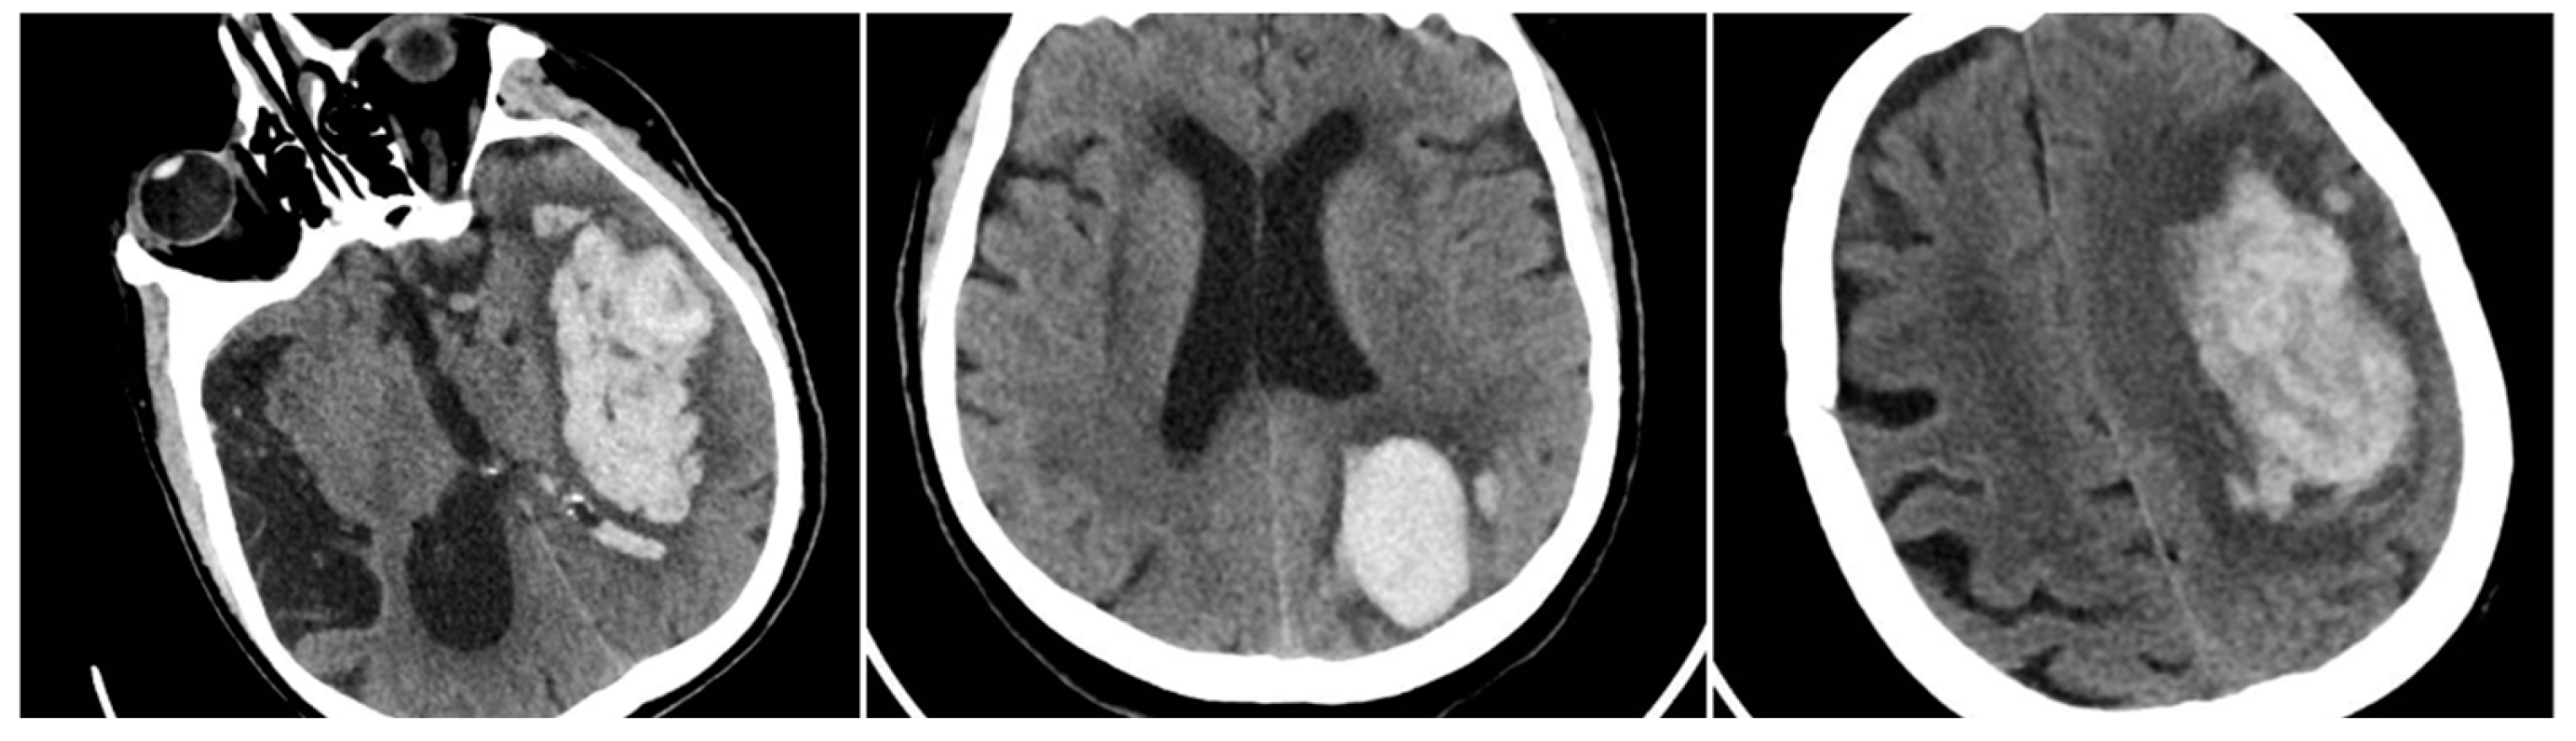

Subgroup analysis based on comorbidities and medication use revealed additional insights (Table 4). Notably, patients with chronic kidney disease and those with thrombocytopenia had the highest mean SUM_BBIS (1.60 and 1.68, respectively), each significantly exceeding the overall mean of 1.25 (p<0.05). Chronic alcohol consumption was also associated with a higher average (1.50). Conversely, statin therapy correlated with a lower SUM_BBIS of 0.92. Within the anticoagulated subset, there was a trend toward more heterogeneous bleeding in warfarin (vitamin K antagonist) users (BS=9.0%, BHS=59.1%, IRS=59.0%, SS=28.5%, mean SUM_BBIS=1.48) compared to DOAC users (BS=13.8%, BHS=37.9%, IRS=55.2%, SS=35.7%, mean SUM_BBIS=1.32), though the difference in total score did not reach significance in this sample (p>0.05). Nevertheless, the Black Hole Sign was conspicuously frequent (59.1%) among warfarin-related hemorrhages, aligning with the possibility that deeper or more unstable bleeds occur under poorly controlled anticoagulation (Figure 7).

Figure 7. Cranial CT scan performed in the ED for a patient with an ICH who had been on apixaban therapy. Left: The head CT scan shows a 70 ml large left capuso-lenticular hematoma; Right: The head CT scan shows a black hole sign (red circle) and margin irregularities (light-blue line).